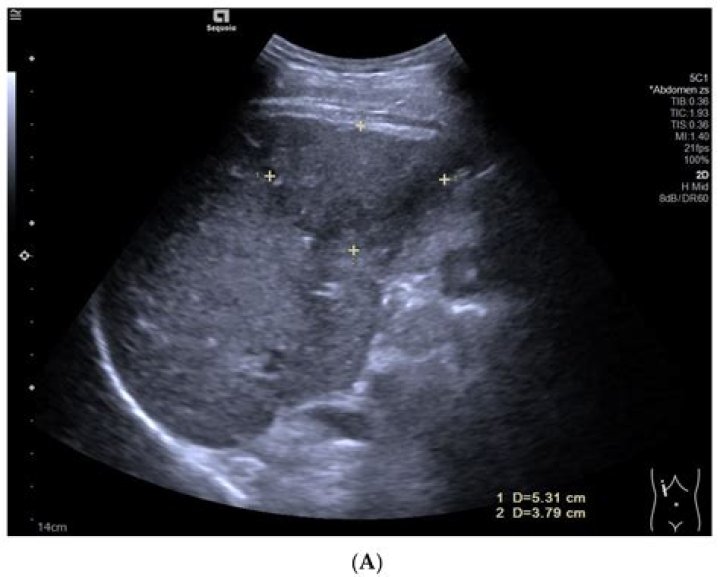

Benign liver lesions usually don’t cause any symptoms. Many people only find out they have one when they go for an imaging test, like an ultrasound, for a different health issue.